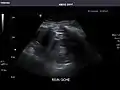

Aorta: Visualized portions normal in caliber, 16 x 15 mm.

Aorta